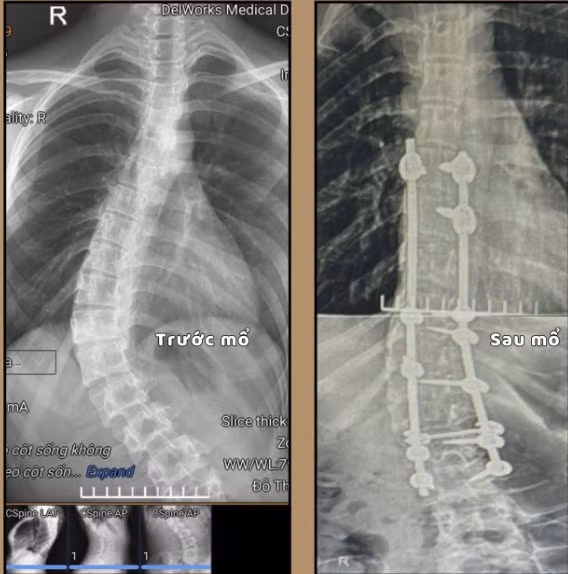

Hình ảnh cột sống cong vẹo trên phim chụp trước và sau mổ - Ảnh BVCC

Khi vào viện được các bác sĩ thăm khám và cho làm các xét nghiệm cần thiết. Kết quả chụp cắt lớp vi tính cho thấy: Hình ảnh vẹo cột sống/nẹp cố định đốt sống từ D6 đến L3. Gãy cung sau một số thân đốt sống và được chẩn đoán: Vẹo cột sống mức độ nặng, có chỉ định phẫu thuật chỉnh vẹo cột sống.

Kíp phẫu thuật do bác sĩ CKII Lê Triệu Linh, Phó trưởng khoa Ngoại thần kinh – Lồng ngực, Bệnh viện Bãi Cháy cùng ê-kíp phẫu thuật đã tiến hành phẫu thuật giải phóng cấu trúc biến dạng, chỉnh trục cột sống và cố định bằng các thanh nẹp – vít chuyên dụng. Sau mổ, cột sống được đưa về trục cân đối tự nhiên, giải phóng áp lực lên các rễ thần kinh.